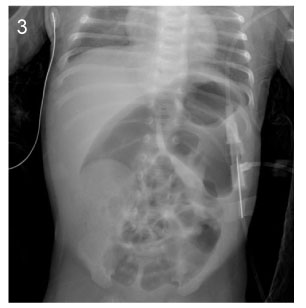

Fig. 2

Image of barium enema at the age of 8days (Case No. 3).

The contrast cannot advance further.

Fig. 2 Image of barium enema at the age of 8days (Case No. 3). The contrast cannot advance further.